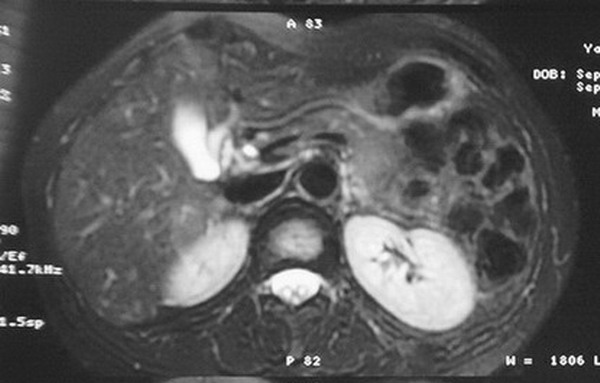

标题: MRI2066:腹膜后占位,请会诊,CT18531近期扫描图像

无明显不适,体检发现,

mri基本排除血管类肿瘤,明显强化说明极富血供,临床无症状,考虑胰岛细胞瘤可能大。

强化明显,并见有血管与之相连;考虑巨淋巴增生症.

极富血供的占位性病变,首先考虑良性,期待结果。